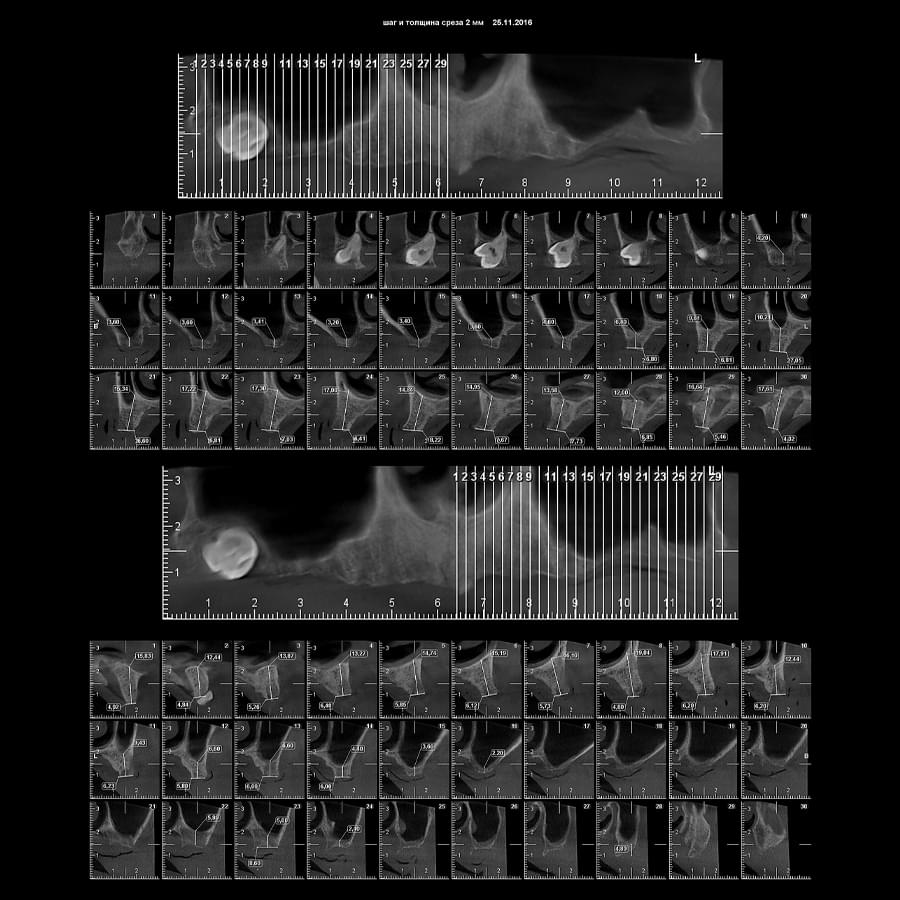

Зуб — це не просто монолітний об'єкт, а складна система мікроканалів. На плоскому 2D-знімку вони часто перекривають один одного, створюючи ілюзію простої анатомії.

Непомічений канал — це джерело майбутньої інфекції та причина «загадкового» болю після лікування. Завдяки високій роздільній здатності обладнання MyRay, лікар бачить кожен мікронний канал ще до того, як візьме до рук інструмент.